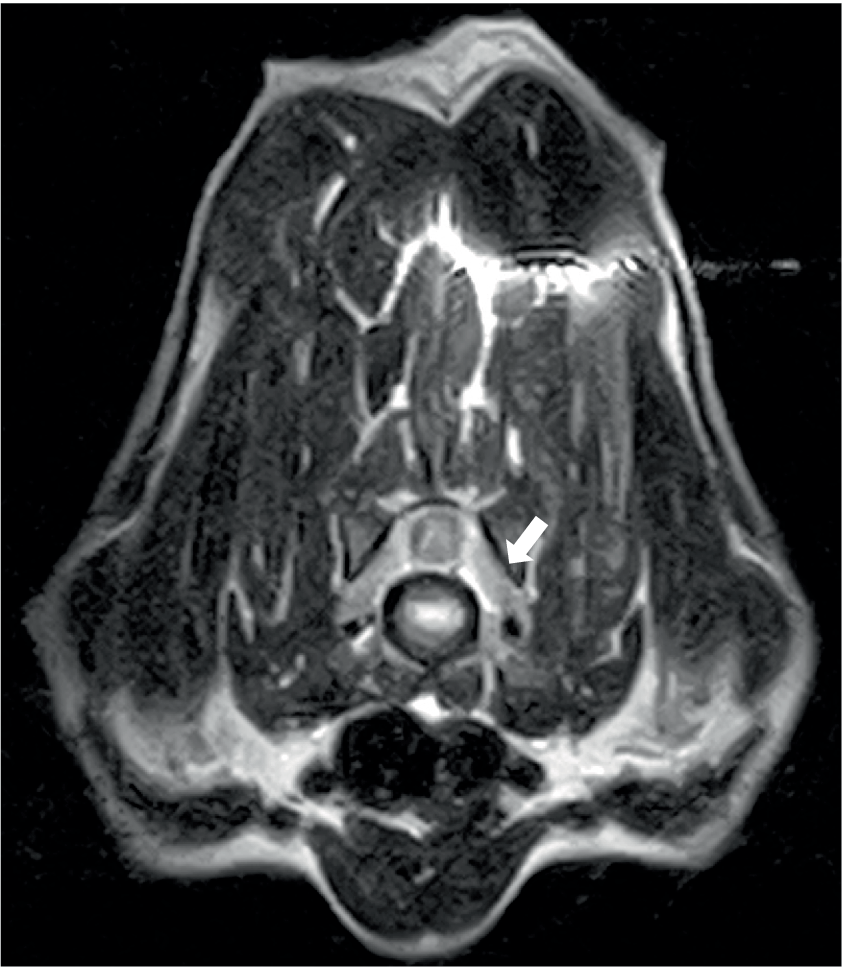

Two dogs underwent spinal MRIs. The cervicothoracic spine study included sagittal T2W, STIR, pre- and post-contrast T1W, and transverse T2W and STIR images, which showed moderate, diffuse, spinal cord swelling of C3-C5 with subtle, patchy cord hyperintensity as observed in STIR. The thoracolumbar study included sagittal and dorsal T2W and sagittal and transverse STIR images, and in the same dog, a lumbosacral study included sagittal T2W, STIR, and T1W, and transverse and dorsal T2W. There were no abnormalities noted in the spinal cord at either site. Both the dogs had evidence of spinal nerve inflammation; in the first dog, this was bilateral and multifocal (Figure 2) and the other dog had a thickened spinal root at L1 within the vertebral canal. In both cases, the adjacent musculature (epaxial or longus colli) showed severe, bilateral, well-defined, asymmetric hyperintensity (Figure 3). One dog was considered to have an equivocal absence of meningitis, and the other had dispersed epidural changes suggestive of meningitis or empyema. One dog had splenomegaly.

Figure 2

Transverse T2W image at the level of the C6-7 disc space in a 9-year-old Spaniel cross showing diffuse thickening of the C7 spinal nerves (arrowed) and/or surrounding soft tissues.